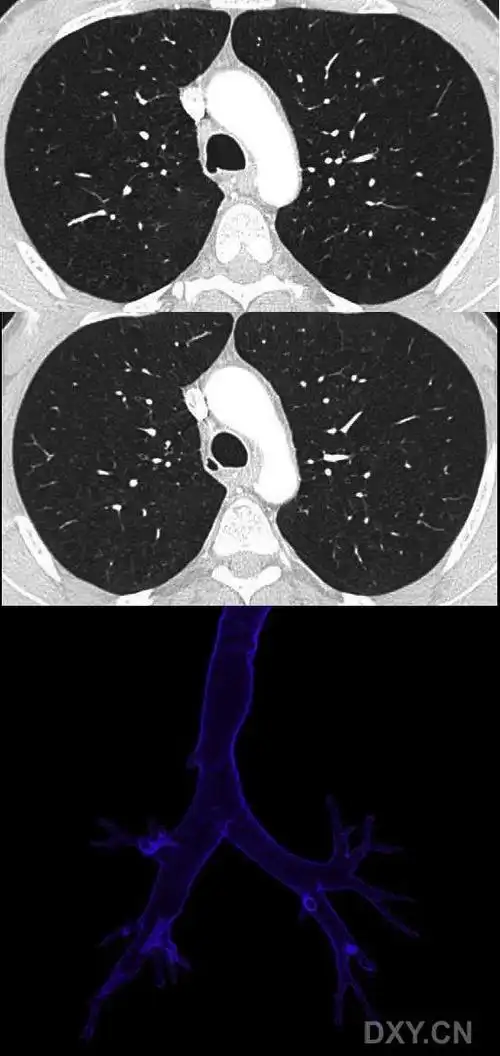

【影像读片】气管憩室ct三维重建 [病例帖]